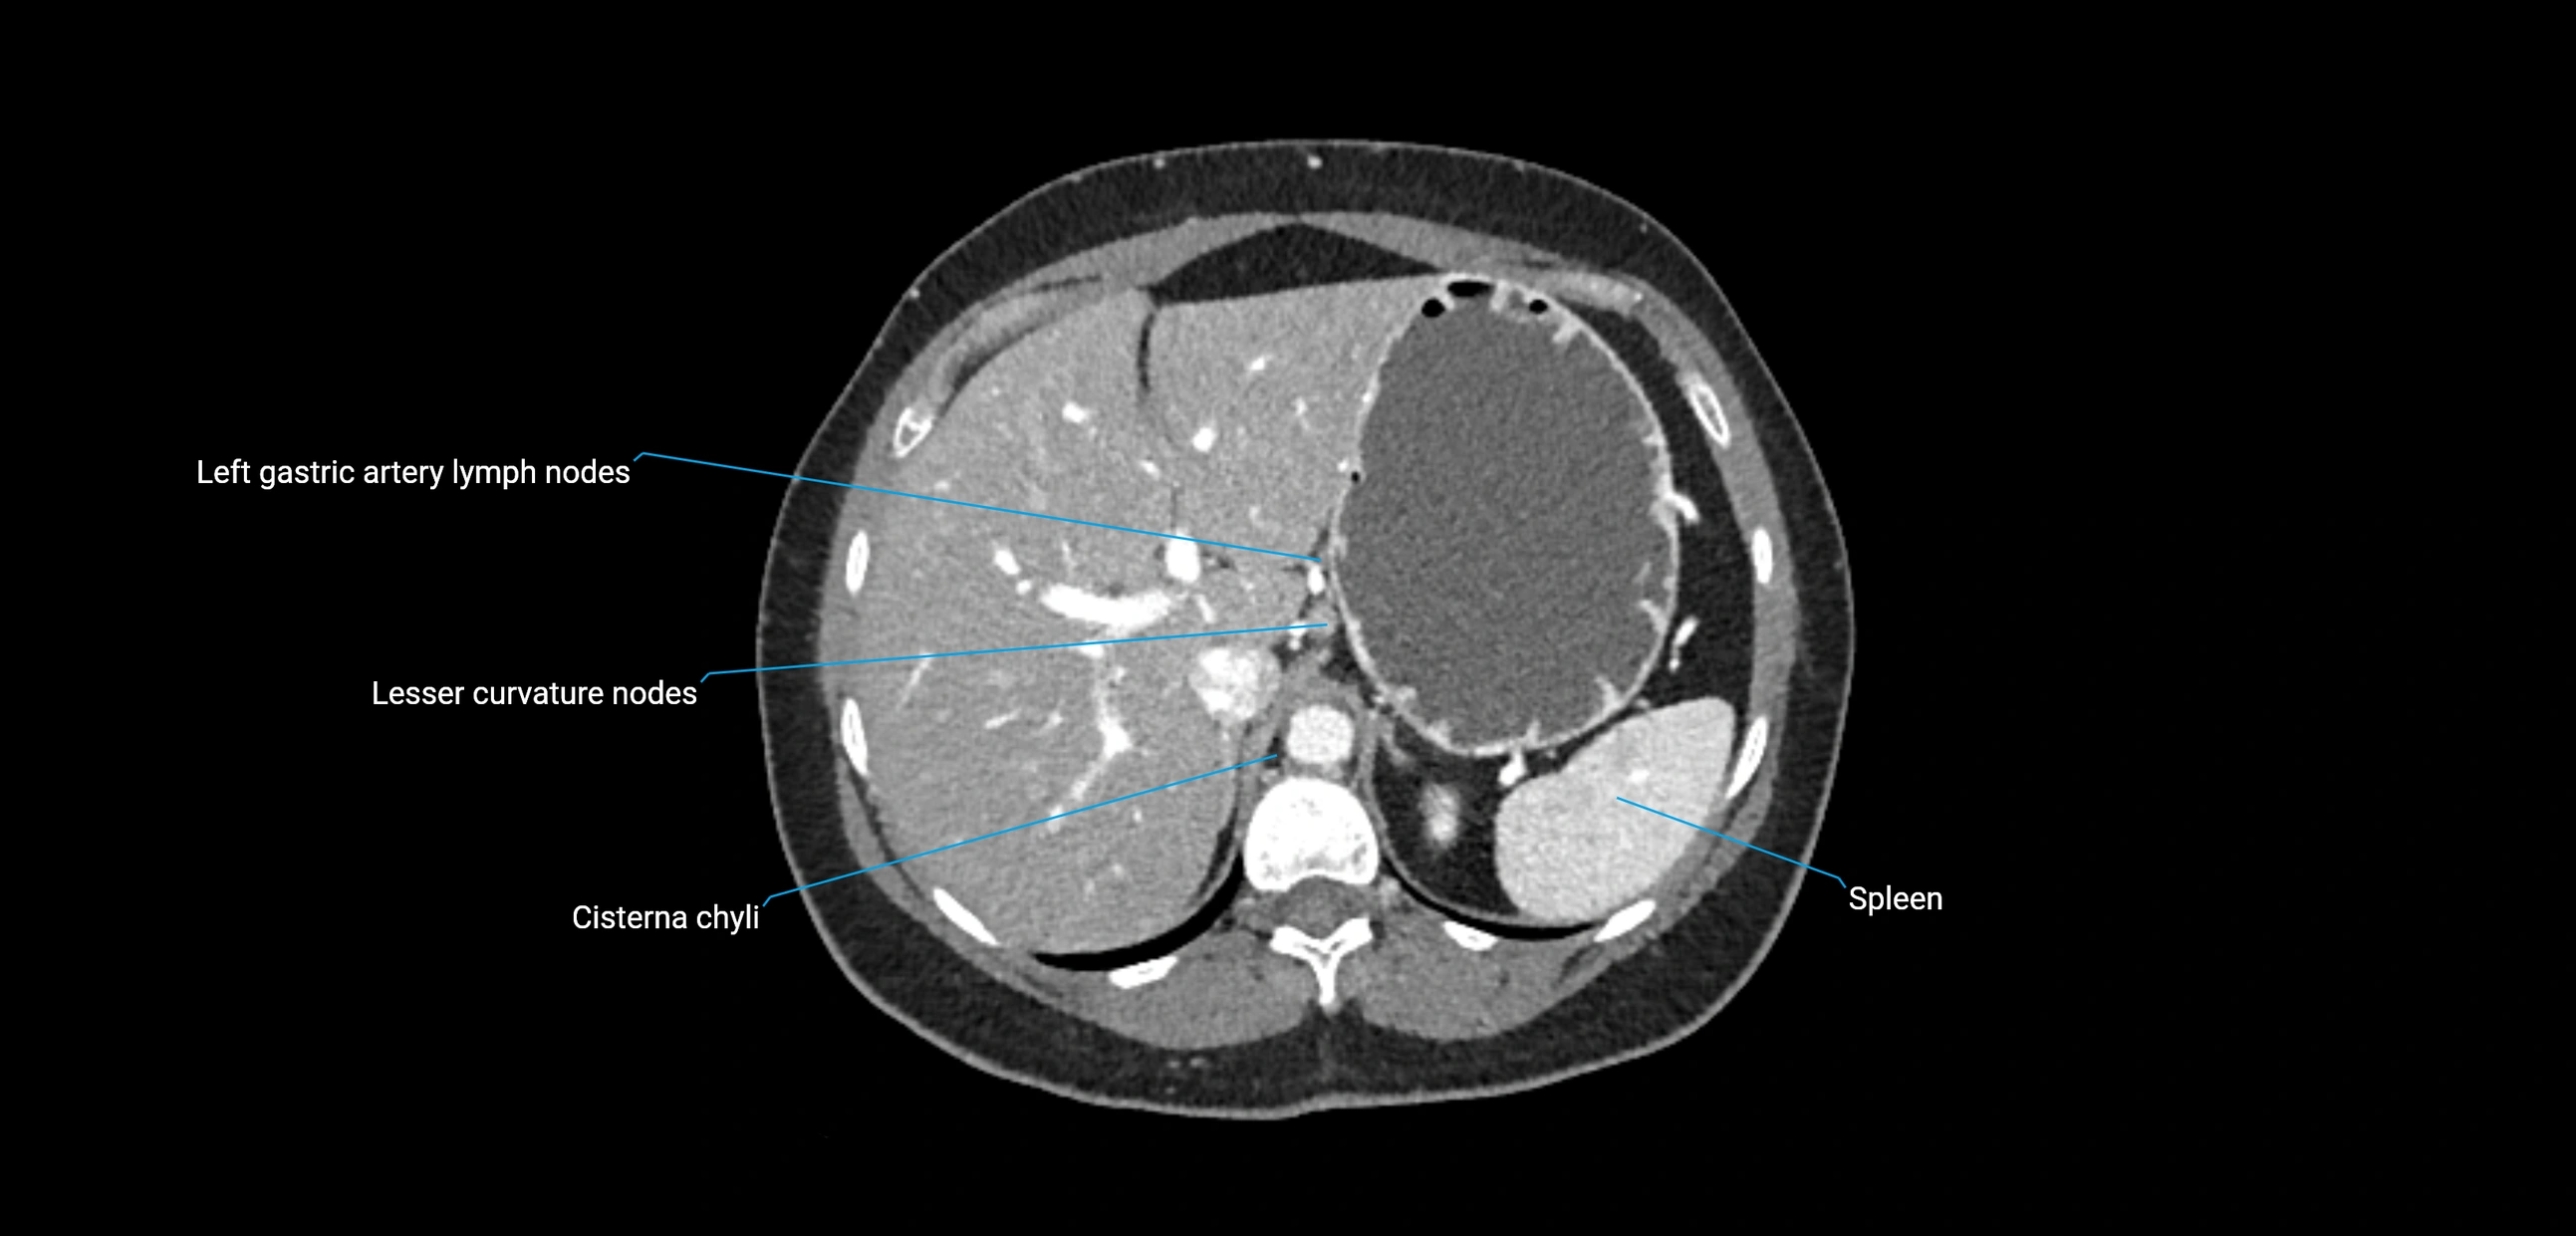

MRI images

image